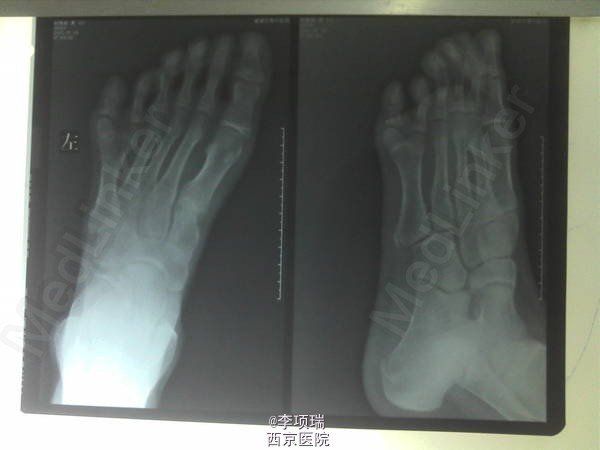

求支招:左足多趾一例

多趾

患者男,16岁,左足多趾,目前目前第六趾处穿鞋磨脚、疼痛不适,要求行足趾去除.拟取第五个,因为它属于正常第五趾赘生物,先天DNA链改变。应该从第五趾骨变异处予以切除。看各位大神有什么高招?